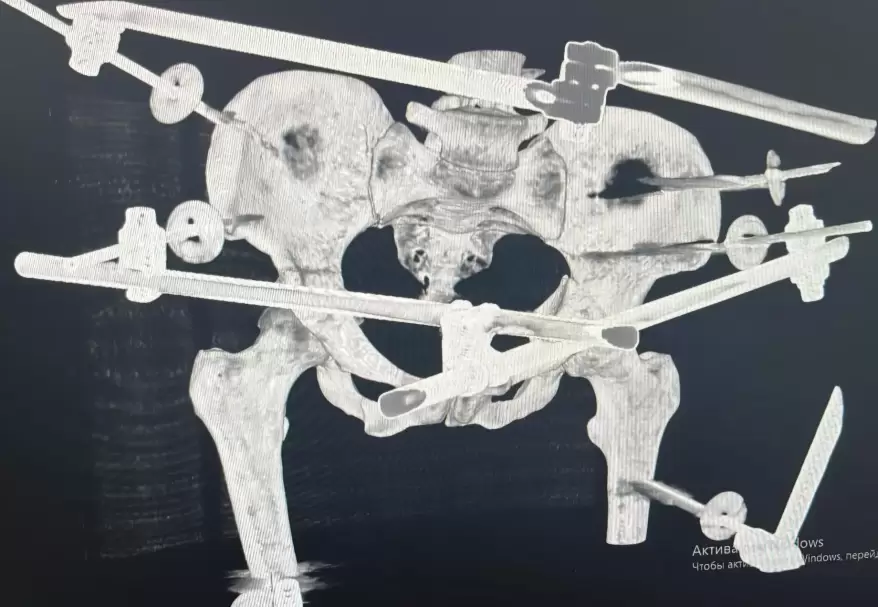

Как сообщает "Вести: Приморье" со ссылкой на Минздрав Приморья, благодаря оперативной и слаженной работе бригады скорой медицинской помощи удалось спасти молодую девушку с крайне тяжёлыми травмами. Пострадавшую экстренно доставили в Спасскую городскую больницу, в травматологическое отделение. Состояние пациентки оценивалось как крайне тяжёлое: травматический шок, открытые переломы костей голени, множественные переломы таза, обширные рваные раны нижних конечностей.

После стабилизации состояния врачи провели сложнейшее оперативное вмешательство — выполнены наружная и внутренняя фиксация переломов таза и голени, лапароскопия для исключения повреждений внутренних органов, а также первичная хирургическая обработка ран. Операция прошла без осложнений», – рассказали специалисты больницы. После этапа реанимации, по согласованию с краевыми медицинскими учреждениями, пациентку перевели в Краевую клиническую больницу №2 для дальнейшей реабилитации.